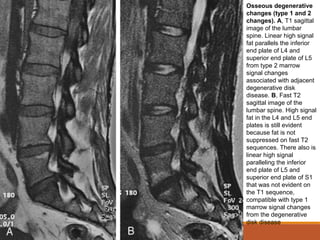

Osseous degenerative

changes (type 1 and 2

changes). A, T1 sagittal

image of the lumbar

spine. Linear high signal

fat parallels the inferior

end plate of L4 and

superior end plate of L5

from type 2 marrow

signal changes

associated with adjacent

degenerative disk

disease. B, Fast T2

sagittal image of the

lumbar spine. High signal

fat in the L4 and L5 end

plates is still evident

because fat is not

suppressed on fast T2

sequences. There also is

linear high signal

paralleling the inferior

end plate of L5 and

superior end plate of S1

that was not evident on

the T1 sequence,

compatible with type 1

marrow signal changes

from the degenerative

disk disease